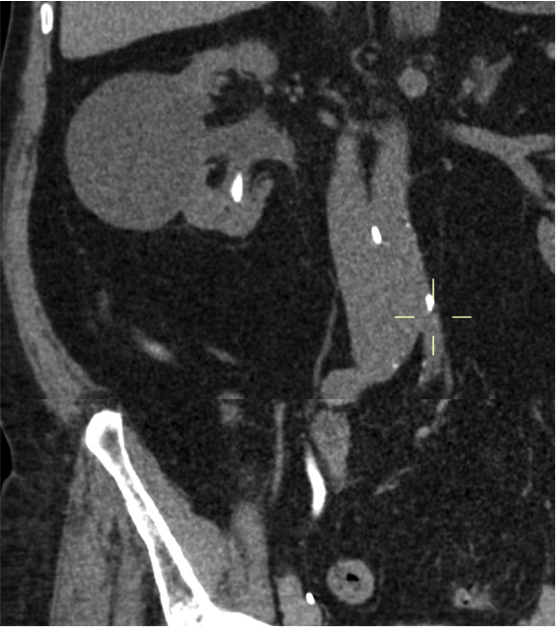

- Líquido en sistema colector de alta atenuación: puede ser dificil distinguir una simple hidronefrosis de una pionefrosis basándonos eclucisvamente en la atenuación del líquido.

- Estratificación del contraste en fase excretora.